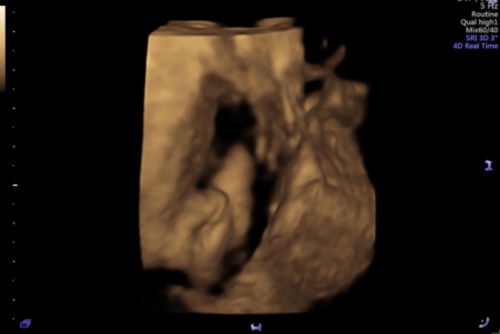

betul ke 4d scan mcm ni baby girl?

Hi mommies semua, sy nak tanya. haritu ada scan 2d masa 22w doc cakap boy. so memang sy pun confident baby boy, baru baru ni scan lagi sbb time tu rasa baby kurang gerak. mula2 scan biasa jee, doc cakap baby girl pulak sbb nampak burger sign. husband xpuas hati terus minta doc buat 4d and nampak sign mcm ni. doc pun dah confirmkan memang baby girl, tapi sy rasa ragu ragu sbb instinct baby boy walaupun memang teringin girl hehe. maaf complicated sikit, harap mommies2 boleh bantu kurangkan keraguan sy 🥲